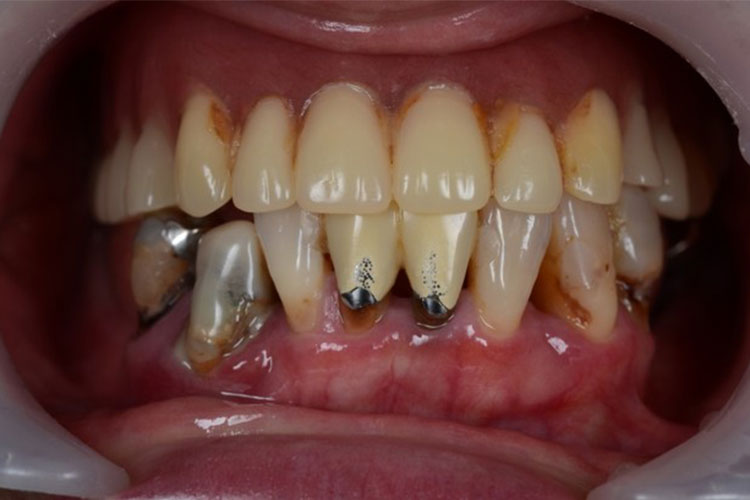

All-on-4症例 Case1

Treatment cases

Before

After

インプラント治療は、咀嚼機能の改善だけでなく、 口腔周囲筋の発達により見た目の若返りにも貢献してくれます。